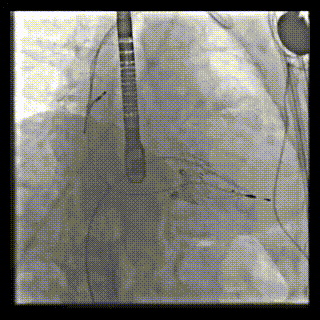

本周三例接受LuX-Valve Plus經血管三尖瓣置換術的患者中,第一例患者為冠狀動脈旁路移植術+Bentall+二尖瓣成形術后;第二例患者為永久起搏器植入術后,存在跨三尖瓣導線;第三例患者合并房顫、房缺及左心耳封堵術后。

三例患者入院后,葛均波院士團隊周達新教授、潘文志教授、張源博士、陳莎莎博士及心超室的潘翠珍教授、李偉教授對患者的情況進行詳細評估和討論,最終決定為三例患者選擇LuX-Valve Plus40mm、50mm和50mm型號的瓣膜進行手術治療。手術后即刻拔除氣管插管,術后患者三尖瓣反流癥狀得到顯著改善,復查心超結果顯示人工三尖瓣瓣膜支架固定穩定,瓣葉關閉形態未見異常,未見明顯反流。

LuX-Valve Plus是LuX-Valve系列產品的第二代,采用的是經血管入路的全新輸送系統,其設計開發過程得到了上海中山醫院葛均波院士及其團隊的精心指導,研究結果提示瓣膜植入的安全性和有效性俱佳,尤其瓣膜獨特的設計使其具有極佳自適應性,本周三例患者病因及解剖結構各具特點,但均可從LuX-Valve Plus植入術明顯獲益。目前,LuX-Valve Plus已在全國各中心開展救治性臨床研究,相信未來定會為更多的三尖瓣反流患者帶來福音。